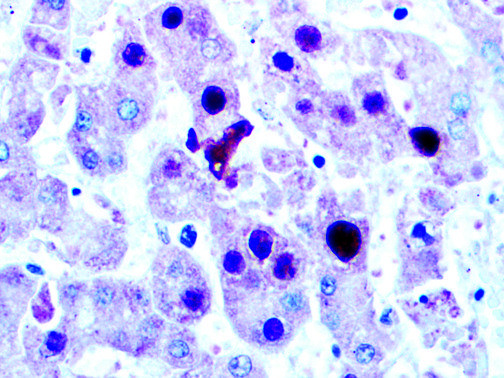

It is the ICU physician who is most likely to witness one of the deadliest manifestations of the abnormal immunological response, the cytokine storm syndrome (CSS). This response is also referred to by some as the cytokine release syndrome (CRS). CSS is characterized by continuous activation and expansion of macrophage and lymphocyte populations, which secrete large amounts of cytokines, causing the cytokine storm. This massive cytokine release is akin to hemophagocytic lymphohistiocytosis (HLH) disease, a syndrome characterized by initial unchecked and persistent activation of cytotoxic T lymphocytes and NK cells.

Clinical and laboratory manifestations of HLH include fever, enlarged liver and/or spleen, neurologic dysfunction, coagulopathy, liver dysfunction, cytopenias (i.e., low levels of erythrocytes, leukocytes, and/or platelets), hypertriglyceridemia, hyperferritinemia, hemophagocytosis, and eventually diminished NK cell activity as the immune system becomes progressively paralyzed. HLH can be familial (primary HLH) or secondary to another disease process (sHLH), such as rheumatic disease, in which it is referred to as macrophage activation syndrome (MAS, characterized by elevated ferritin).